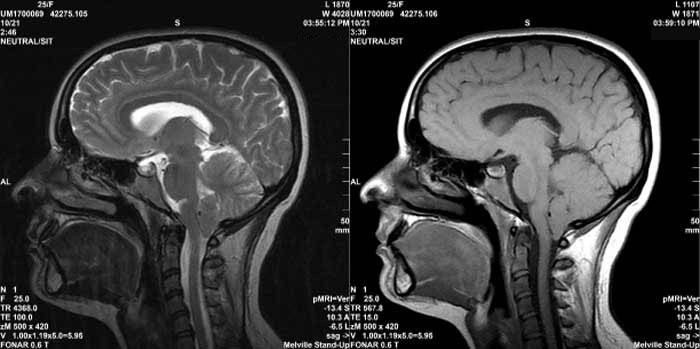

Figure 11.

T2 MRI visualization of a tumor of the brain made possible

by the discovery

of Damadian of the abnormal T2 (and T1) MR (NMR) relaxations

of cancerous tissue.

Figure 14 is an axial (cross-sectional) image of the brain showing a tumor of the cerebellum (white areas) in the midline. Figure 14c is a magnified image showing the picture elements or "pixels" (small squares) that make up the image. The cerebellar tumor as it would appear (D) with no MR signal differences. Figure D is the same image as B but where all MR signal differences were eliminated and all the MR pixels therefore had the same pixel brightness. The absence of the MR signal differences between cancer and normal tissue discovered by Damadian gives the MR image pixels equal brightness and the tumor becomes Invisible. |

Were the amplitudes of the NMR signals (fig.9) used to set the brightness of each MRI image pixel the same for all tissues (and prior to Dr. Damadian's discovery such NMR tissue signal differences were not known to exist) the brightness of each image pixel would be the same. The MR image would be a blank.

The NMR signal differences discovered by Damadian (Figs 6,9,tables 1 & 2) vary the brightness of the pixels that make up the image (Figs. 6,9). The signal differences of diseased and normal tissues generate the large differences in pixel brightness that enable all diseased tissues (cancerous as well as non-cancerous) to be exquisitely visualized (fig.3b,10,11-13) by the MRI image. Additionally the exceptional NMR signal differences among the normal tissues discovered by Damadian give rise to the extraordinary detail of normal anatomy visualized by MRI (figs. 7,8)